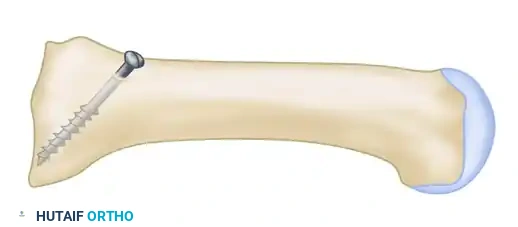

- Pre-drilling the Glide Hole: Crucial Step. Drill a 3.5-mm glide hole at the 2-cm mark (1 cm distal to the planned osteotomy) in the center of the metatarsal shaft, directing it proximally. Performing this before the osteotomy ensures absolute stability during drilling.

- Executing the Osteotomy: Use a specialized curved crescentic saw blade. The convexity of the blade must face distally.

- Biomechanics: A distally convex cut prevents overcorrection of the intermetatarsal angle and minimizes shortening of the first ray.

- Score the dorsal cortex, then gently rock the blade medially and laterally. Ensure the lateral aspect of the blade exits the lateral cortex cleanly. The medial cortex can be finished with a small osteotome if necessary.

- Place a centering device ("golf tee" or "mushroom" guide) into the pre-drilled 3.5-mm glide hole.

- Drill the proximal fragment with a 2.0-mm or 2.5-mm drill bit.

- Tap the proximal fragment with a 4.0-mm tap.

- Insert a 4.0-mm fully threaded cancellous screw (typically 26 mm in length).

Clinical Pearl: Countersinking is Mandatory

Use a countersink in the dorsal glide hole before inserting the screw. This gently removes cortical bone from the distal hole, allowing the screw head to sit flush. If omitted, the screw head will abut the dorsal cortex during the final turns, acting as a wedge that will inevitably fracture the intervening cortical bone bridge, leading to catastrophic loss of fixation.